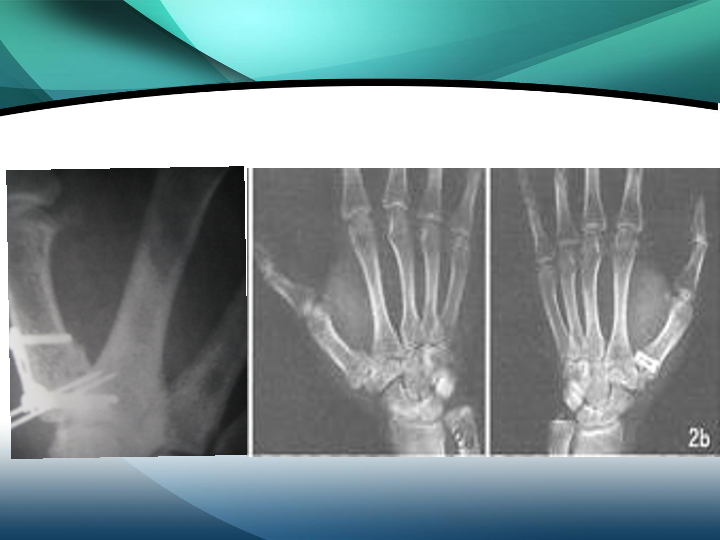

掌骨骨折